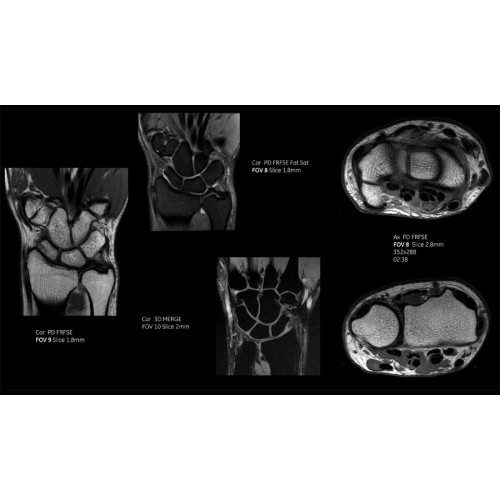

Система SIGNA Pioneer воплощает поразительные достижения в области визуализации. Передовая технология Total Digital Imaging (TDI) позволяет добиться большей четкости изображений и на четверть повысить соотношение сигнал/шум.

• Технология Direct Digital Interface (DDI) использует независимый аналого-цифровой преобразователь для оцифровки сигнала от каждого из 97 радиочастотных каналов, что обеспечивает значительное увеличение качества за счет уменьшения фонового шума.

• Технология Digital Micro Switching (DMS) — это следующее поколение технологий радиочастотных катушек, основанное на замене аналоговых схем блокировки сверхбыстрыми микропереключателями (MEMS), что делает возможным быстрое переключение катушек для дальнейшего расширения возможностей визуализации с нулевым TE.